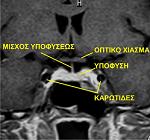

ΣΚΛΗΡΥΝΣΗ ΚΑΤΑ ΠΛΑΚΑΣ ΚΑΙ Ο ΜΙΣΧΟΣ ΤΗΣ ΥΠΟΦΥΣΗΣ

Η ΥΠΟΦΥΣΗ ΕΙΝΑΙ ΈΝΑΣ ΚΕΝΤΡΙΚΟΣ ΑΔΕΝΑΣ ΤΟΥ ΣΩΜΑΤΟΣ ΠΟΥ ΚΡΕΜΕΤΑΙ ΑΠΟ ΈΝΑ ΜΙΚΡΟ ΜΙΣΧΟ ΑΠΟ ΤΟΝ ΥΠΟΘΑΛΑΜΟ ΤΟΥ ΕΓΚΕΦΑΛΟΥ.

Το σύστημα αυτό, όλο μαζί, συντονίζει τη ρύθμιση των ορμονών και πολλών εγκεφαλικών λειτουργιών, αναγκαίων για τη ζωή και την ομαλή λειτουργία του σώματος. Μια διαταραχή του συνδυασμού αυτού είναι π.χ. ο άποιος διαβήτης. Στη σκλήρυνση κατά πλάκας τυχαίνει πολλές φορές, λόγω ύπαρξης μιας απομυελυνωτικής εστίας σε αυτή την περιοχή, να έχουμε παρόμοιες διαταραχές, οι οποίες βέβαια χρειάζονται και επιπλέον φροντίδα. Σε αυτές τις περιπτώσεις, θέλει με επιμέλεια αυτές οι διαταραχές να εξετάζονται με προσοχή, διότι θέλουν ιδιαίτερη μεταχείριση και να μην εκλαμβάνονται σαν σύνολο των προβλημάτων της σκλήρυνσης κατά πλάκας. Η θεραπεία πρέπει να είναι πιο διαφοροποιημένη.